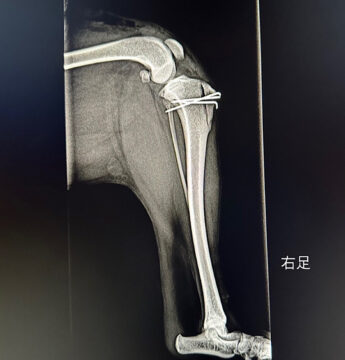

お願い 2024.09.10 パテラ(膝蓋骨脱臼)グレード3の手術を終えました ▶︎ 続きはブログへ 毛呂山ブリーダー事件で保護されたトイプードル系の女の子3頭を、当会で迎えることになりました。 そのうち1頭は、後ろ足を引きずるような歩き方や、膝を曲げて腰を落としたような姿勢で歩くなど、歩行に異常が見られていました。動物病院での診察の結果、パテラ(膝蓋骨脱臼)でグレード3であることが判明し、緊急手術いたしました。 皆様からの手術費への温かいご支援を心よりお願い申し上げます。 あかねちゃんの詳細はこちら 2023.04.14 2026.02.13 あかねちゃん(募集停止中) 里親選考中のため募集停止中です (キャンセル待ちは受付中) 【名前】あかねちゃん 女の子♀ 【推定誕生日】 2019年8月28日() 【犬種】トイプードル 【体重】約5.5kg 見学希望の方はこちら... 里親選考中のため募集停止中です (キャンセル待ちは受付中) 【名前】あかねちゃん 女の子♀ 【推定誕生日】 2019年8月28日() 【犬種】トイプードル 【体重】約5.5kg 見学希望の方はこちら... Post ブリーダー事件で保護されたプードルちゃんたちへご支援のお願い 前の記事 ボランティア募集再開のお知らせ! 次の記事